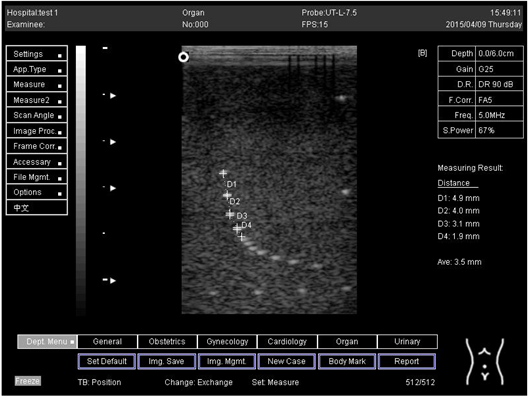

6.0 Axial resolution

Biomimetics 07 00130 i013

D1 = 3.0

D2 = 2.0

D3 = 1.0

D4 = 0.6

6.0Lateral resolution

Biomimetics 07 00130 i014